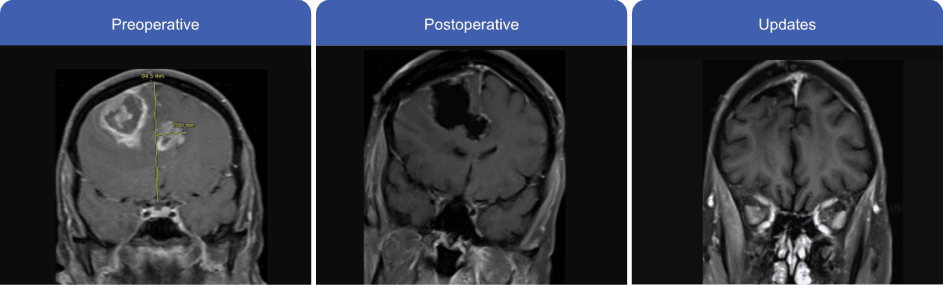

Patient's MRI

Case information used with permission from Kellie Kopp, RN, BSN, OCN.